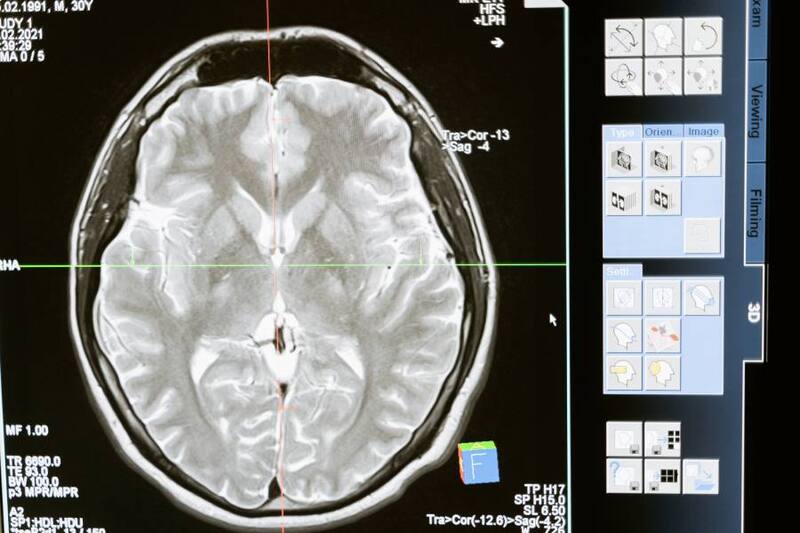

Por medio de resonancias magnéticas en pacientes que habían padecido de Covid, pero que quedaron con secuelas de este virus, tienen mayor mayor probabilidad de desarrollar daños en algunos de sus órganos vitales.

"Cinco meses después de ser dados de alta, las resonancias magnéticas de sus órganos principales mostraron algunas diferencias significativas en comparación con un grupo de 52 personas que nunca habían tenido Covid", reveló la BBC.

La doctora Betty Raman enfatizó en que las personas que estuvieron el virus en el cuerpo tienen una mayor probabilidad de tener daños importantes en sus riñones, en su cerebro y en los pulmones, que alguien que no lo tuvo.

"Nuestros hallazgos también resaltan la necesidad de servicios de seguimiento multidisciplinarios a más largo plazo centrados en la salud pulmonar y extrapulmonar (riñones, cerebro y salud mental), particularmente para aquellos que fueron hospitalizados por el covid", informó Raman.